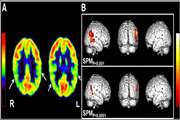

بررسی همبستگی نتایج آنالیز کمّی و کیفی در تصویربرداری PET/CT بیماران صرع لوب تمپورال در ایران 1404/08/12 - 11:46